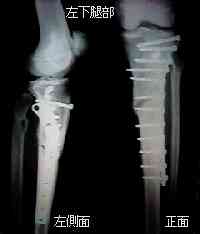

診察の結果”左下腿骨粉砕骨折”そして右足も”下腿骨単純骨折”

と判明した。 診断書より

右足の単純骨折部はやはり”すね”で、病院でレントゲンを撮るまでは打撲と 思っていた程、痛みは無かった。 現在ギブスにて固定、ギブスを外して体重を 支えられるまで6週間程かかる見込み。左足は”すね”の複雑骨折で、まだ内出血が止まってない (?)様な状態で、状態が落ち着くと思われる来月5日に手術し、ボルトにて固定する。その後 1週間ほど様子を見て仙台(名取)へ移動する。

手術は3時間かかったそうです(予想よりかかったみたいです) 今左足に13本のボルトが入っていて、そのままギブスではなく 板の上に足がある状態で包帯で縛られています。 手術後麻酔が切れ掛かった時かなり痛かったらしく、騒いでいたら 婦長さんに怒られていたみたいです。 昨日の様子は、昼間はほとんど点滴をしている状態で、 たまに、いろいろな痛みが走るみたいです。 足の傷自体だけじゃないみたい・・・ 右足も、ひねりはダメみたいですが、 上下には少し動かせるようになっていました。 なんか行動範囲を広くしようとがんばっていました。 こちらへの転院ですが、動かせるようになってからみたいなので、 手術後1週間は盛岡に滞在していそうです。

この手術により左足は、鉄板一枚+ボルト13本の改造人間になっ

てしまった!

感想としては、手術後麻酔から覚めたときの痛みはたいへんなものだったが、

ゲレンデでブ−ツを脱がされたときに比べたらたいしたことがなかった。この鉄板+ボルトとは約1年間のおつきあいとなるそうです。(T_T)